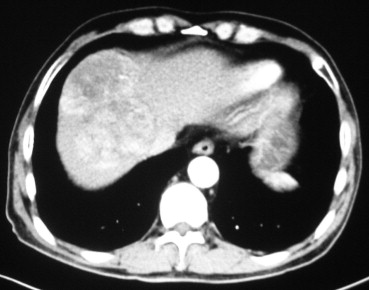

The outcome of 60 consecutive patients who underwent hepatectomy with inflow blood exclusion (Pringle maneuver) and infrahepatic IVC clamping (Group A) between June 2010 and July 2012 was compared with that of 53 consecutive patients who received hepatectomy with Pringle maneuver only between January 2007 and April 2010 (Group B). All patients were operated on for tumors involving hepatocaval confluence, which was assessed by abdominal ultrasonography, abdominal computed tomography, and/or magnetic resonance imaging (Fig. 1). Liver function was assessed using Child–Pugh grading, serum liver biochemistry tests, and indocyanine green clearance test. Only Child–Pugh class A patients were considered for major hepatectomy (resection of ≥3 liver segments). Exclusion criteria were as follows: extrahepatic metastases in patients with malignancy, peripherally located lesion that did not involve hepatocaval confluence, tumors originating in the caudate lobe, or patients with severe comorbid conditions.

Abdominal computed tomography image of a 9-cm tumor located in segment 8.